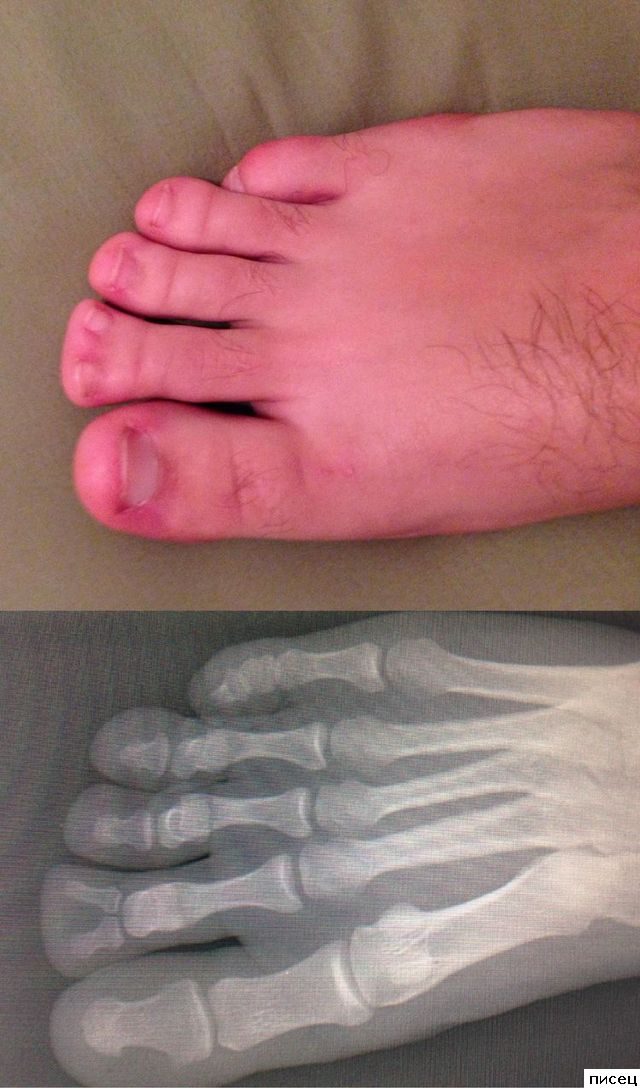

Ну первое фото прям подарок, не надо ногти постоянно стричь